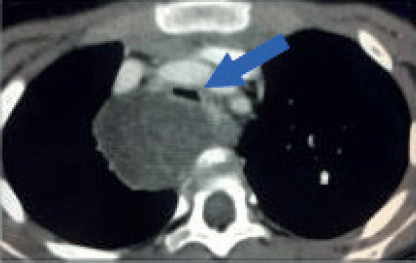

Feasibility and Outcomes of MIS in Mediastinal Tumours in Children 51

Feasibility and Outcomes of MIS in Paediatric Patients with Lung Metastases 52

Open versus thoracoscopic approach for pulmonary lesions in Osteosarcoma 53